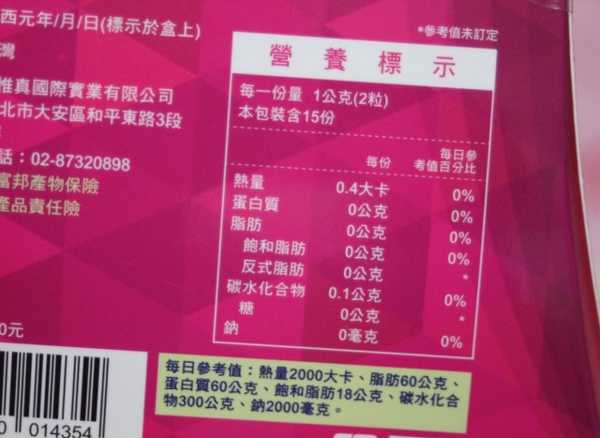

每一盒Supercut塑魔纖立塑膠囊都有三小包,每一小包有10顆膠囊

Supercut塑魔纖立塑膠囊的成分有:瓜拿那萃取粉、肉桂萃取粉、辣椒萃取物(唐辛子)、吡啶甲酸鉻、番瀉葉粉末、玉米澱粉、氧化鎂、二氧化矽。

食用方式:早晚餐前30分鐘各1粒,每日不超過2粒。(多食無益)

番瀉葉萃取物每日食用限量為12mg以下,